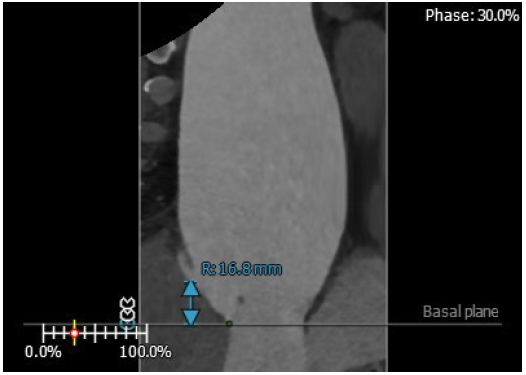

3. 患者左侧冠脉开口高度低LCA:3.1mm,左冠瓣瓣叶长度约12.4mm;右侧冠脉开口高度可RCA:16.8mm;

右冠高度:16.8mm